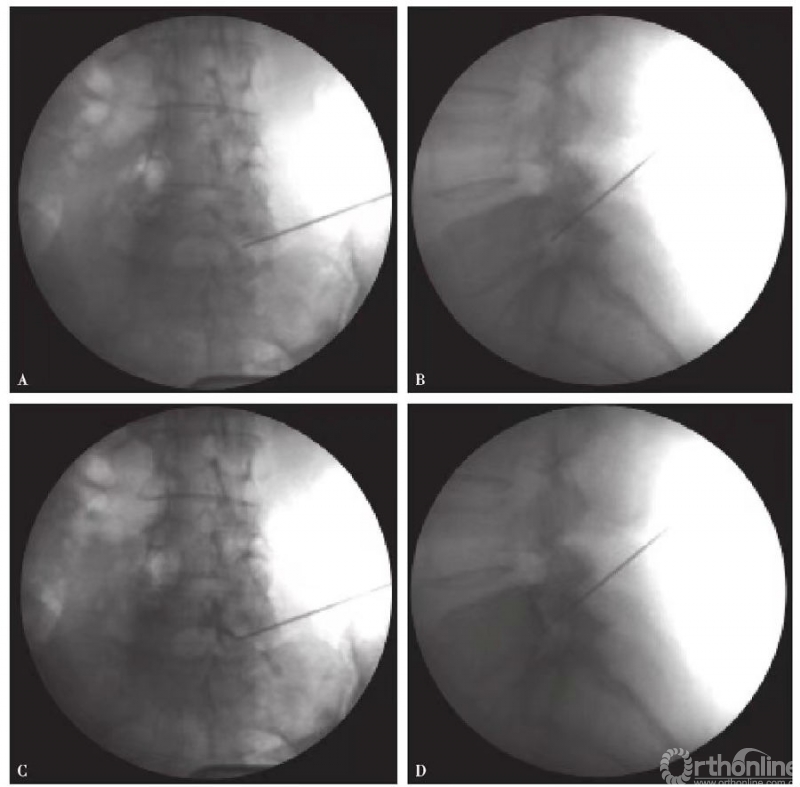

(3)术者置入穿刺针后,首先,到达目的神经根头侧颈椎的横突前结节A点,然后稍微回退,躲开前结节再向内、尾侧刺入,到达B点,目的神经沟的管状骨性结构。穿刺到目的神经根即可诱发相应的放射痛(图4A);

(4)注入造影剂1~2ml(通常为水溶性,如碘海醇),X线透视,观察神经根显影(图4B);

图4 颈椎C6神经根选择性穿刺造影 A.穿刺示意图;B.C6神经根造影图说明:由于颈椎C1和C2解剖特殊,本操作步骤仅适合C3~7神经受压引起的神经根性疼痛的定位诊断和神经阻滞治疗。